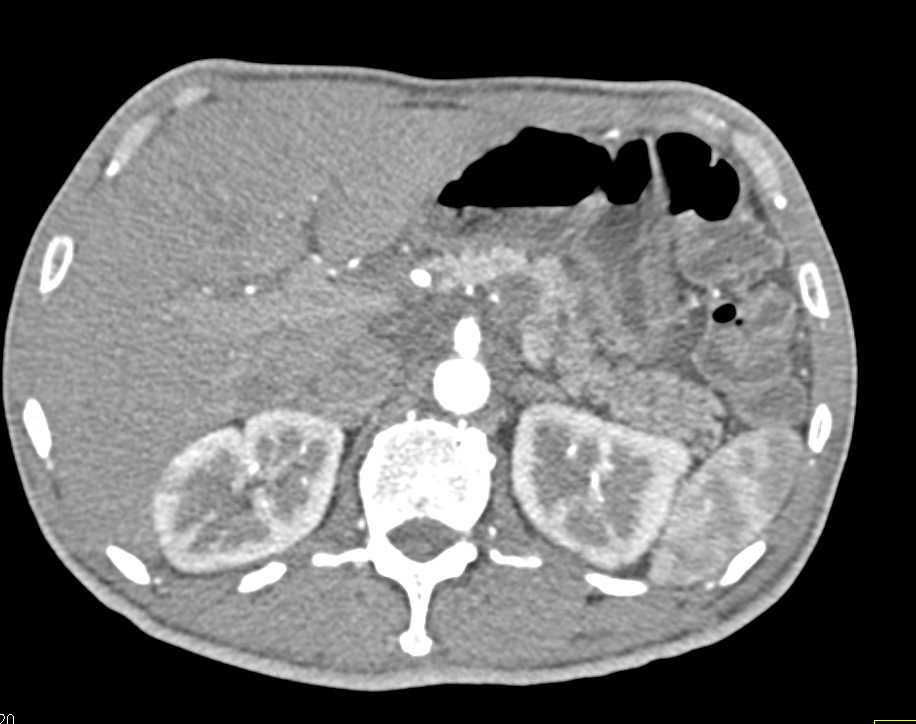

Pancreatic Cancer and Hemangioma Liver